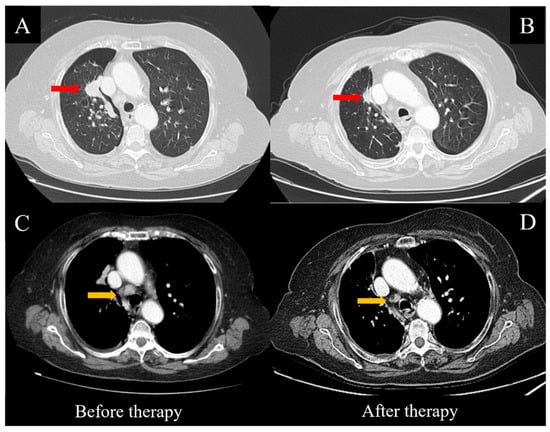

2. Case Report